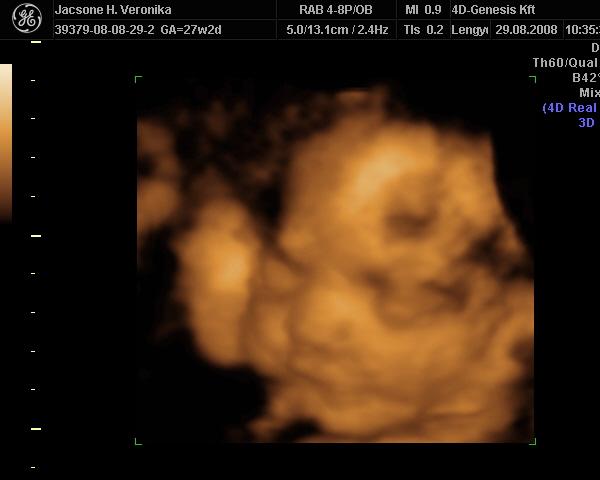

30. hét: Kép Kép

Bernuska: nekem csak a doki magánrendelésén van UH. Én nem járok máshová. Kérdeztem erről a védőnőt is, de ő azt mondta a doki elég. Mondjuk ott nagyon jó minőségű UH van, a környék legjobb 4D-se (amúgy is csak a kórházban van, az meg pocsék). Szívhangot nem néz, de a védőnő mindig nézi. Most azért is mért a doki, mert ez protokoll UH volt, így a 30 .hét környékén, a súlyt csak saccolta, de azt mondta, hogy ott nagyot lehet bukni. 3 hete például megnézte a méhszájamat, és akkor is UH-zott csak nem mért. Akkor végignézte a feje búbjától a kis talpáig az egész gyerkőcöt, és ott külön megnézte a szívét. Ja és mindjárt az elején mikor megnézte a fejecskéjét áttette 4D-re és akkor kaptunk róla egy szép képet. Most is megvizsgált, tökéletesen zárt minden, aztán UH-zott. Megint a fejével kezdte, átrakta 4D-re, úgy nézegettük egy kicsit és jókat nevettünk a dokival. Teljesen eltakarta magát a gyerek és fintorgott. A doki is megjegyezte, hogy milyen kis helyes. Aztán nagy nehezen az egyik kezét elhúzta, és azt a képet kinyomtatta a doki (nemsokára felteszem), Ezután visszakapcsolta sima UH-ra és megmérte! Utána meg kérdezhettem, amit akarok. Nagyon-nagyon segítőkész a dokim, bármikor hívhatom. Pedig én nagyon féltem, mert nincs még egy éve hogy hozzá járok. Előtte 10 évig egy másik dokihoz jártam, akit nagyon szerettem, de elment nyugdíjba és szülést nem vállal. Akkor találtam rá a mostanira. Eddig minden ok vele. Ja és szerintem nem is drága, mert 5000Ft egy vizsgálat. Itt a környéken más dokik is elkérnek ennyit, aztán még UH-juk sincsen. Ja van internetes oldaluk is www.medi-centrumszekszard.hu. Itt azért látható, hogy mennyire kultúrált is. Ha látnád az itteni kórházat, háááátttt pocsék!!! :twisted: Elég lesz ott szülni!!!